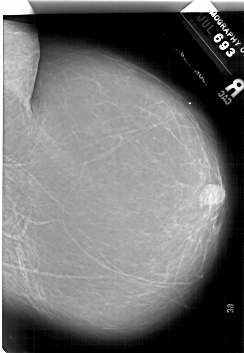

A_1882_1.LEFT_MLO

LEFT_MLO LINES 6736 PIXELS_PER_LINE 5071 BITS_PER_PIXEL 12 RESOLUTION 43.5 OVERLAY